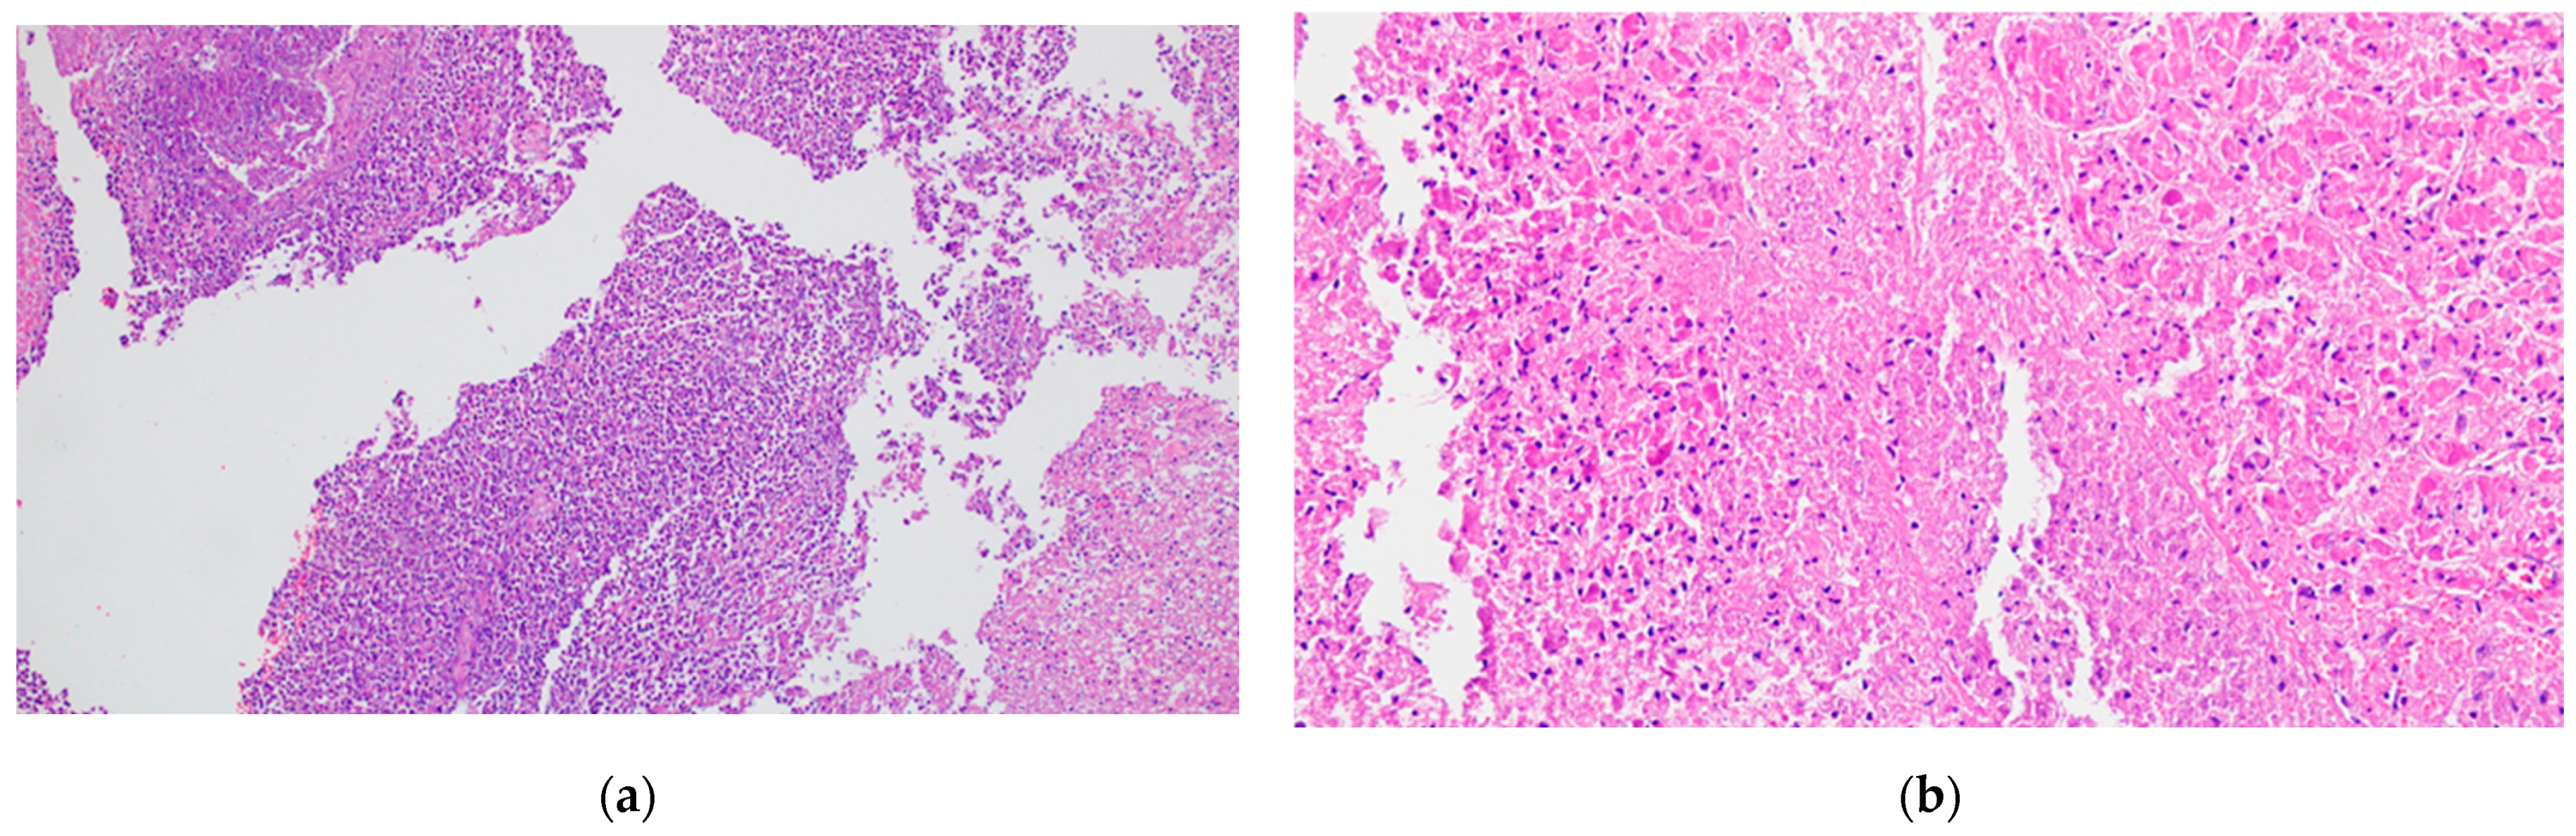

- Intralobular ducts—represented by intercalated ducts that continue the lumen of the acini and are delimited by simple cuboidal epithelium; intercalated ducts fuse to form proper intralobular ducts, which are larger and delimited by simple cuboidal or columnar epithelium; around these ducts, a loose connective stroma can be observed, with numerous reticulin fibers, yet quantitatively reduced overall; unlike major salivary glands, the exocrine pancreas does not have striated ducts (see Figure 4a,b).

- Interlobular ducts—located in connective trabeculae; they have a wide lumen and are delimited by simple columnar epithelium; they are surrounded by well-represented, dense, irregular connective tissue, which contains fibroblasts and myofibroblasts (see Figure 5).